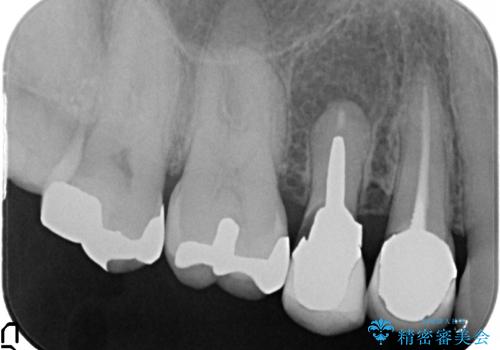

- 右上の奥歯でものを咬むと痛むので診て欲しいといらっしゃった方の症例です。

診査の結果、歯根が破折しており保存不可能だったため抜歯し、ブリッジによる補綴を行いました。